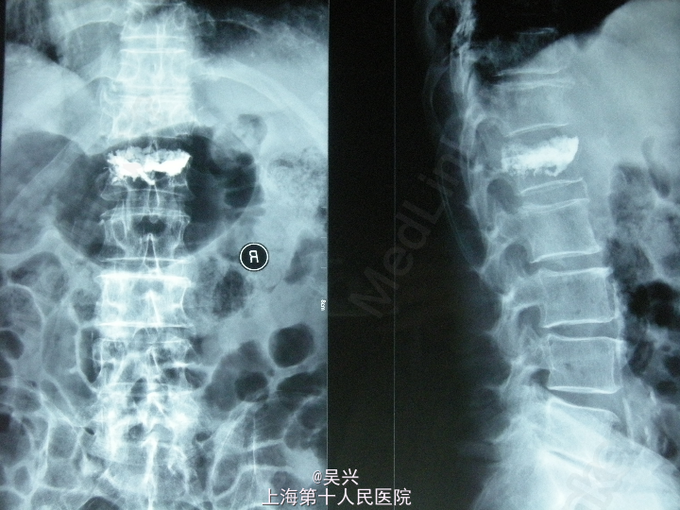

诊断:L1椎体压缩性骨折 处理:入院第二天局麻下行L1压缩性骨折椎体后凸成形术(PKP术)。

随访:术后第1天患者戴腰围下地,疼痛明显缓解,术后1月患者来门诊复诊腰背无疼痛,活动良好。 讨论:老年性腰椎压缩性骨折很常见,既往如果腰椎骨折无神经压迫症状都采用平卧硬板床2~3月等保守治疗,常会导致长期卧床肺炎、褥疮等并发症,而且老年性骨质疏松加重,以后会反复发生骨质疏松性骨折。腰椎椎体凸成形术(PKP术)在治疗老年腰椎骨折方面有很大优势,一般只需局麻,没有伤口,半小时内即可完成,第二天患者疼痛明显缓解,可腰围保护下行走,极大提高了老年人的生活质量,但骨水泥注入不要强化过度,以免发生邻椎病或相邻椎体骨折。